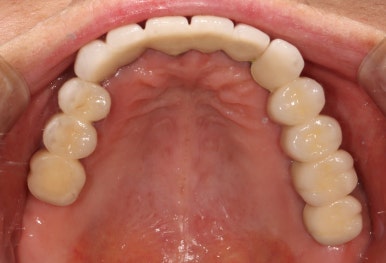

저희 치과와 협업하는 기공소에서 제작해온 임시치아를 장착한 상태입니다.

플라스틱 재질인 레진으로 제작되어 있어 색상은 그닥 수려하지 않으나, 연습용으로 써보기에는 아주 딱이죠?

생각보다 보기에 모양도 괜찮습니다. 요새 임플란트 보철물은 모두 CADCAM으로 지르코니아 블럭을 깎아서 제작하기 때문에, 만약 이 임시치아가 마음에 드셨다면 최종 지르코니아 크라운도 컴퓨터에 입력된 데이터를 이용하여 똑같이 깎아서 제작해드릴 수 있답니다. 이 모든게 치과에서 구강스캐너를 사용하기에 가능하죠..

어쨌든, 어금니 임플란트로 치아가 6개나 새로 제작되었기에 볼이나 혀가 씹히진 않는지 - 식사시에 아프거나 음식이 끼는 것은 없는지 등을 확인하기 위해 약 2-4주 정도 사용해보시게 됩니다.

생각보다 임시치아보다 훨씬 매끈한 표면과 비슷한 색깔을 자랑하는 지르코니아 크라운입니다.

최종 완성된 보철물은 상당히 이상적인 형태를 갖고 있습니다.